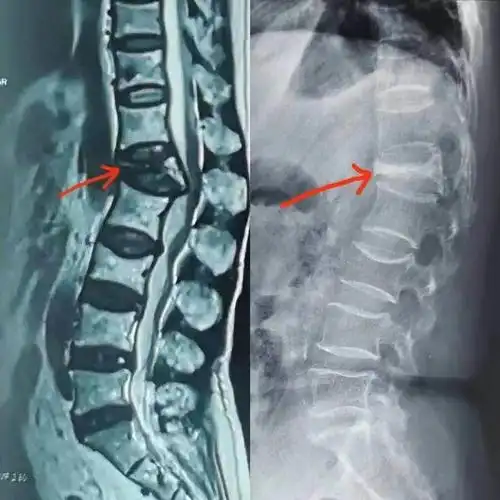

【羊城晚报】老人突发腰痛,骨质疏松椎体骨折要注意!

患者的脊椎正侧位x片